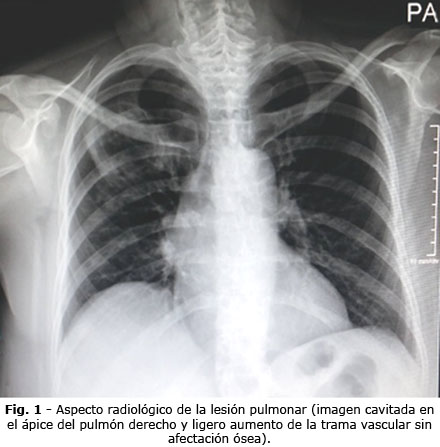

El control radiológico (Fig. 3) mostró mejoría notable del proceso ocupativo; los exámenes de laboratorio confirmaron la mejoría de las pruebas de función renal.